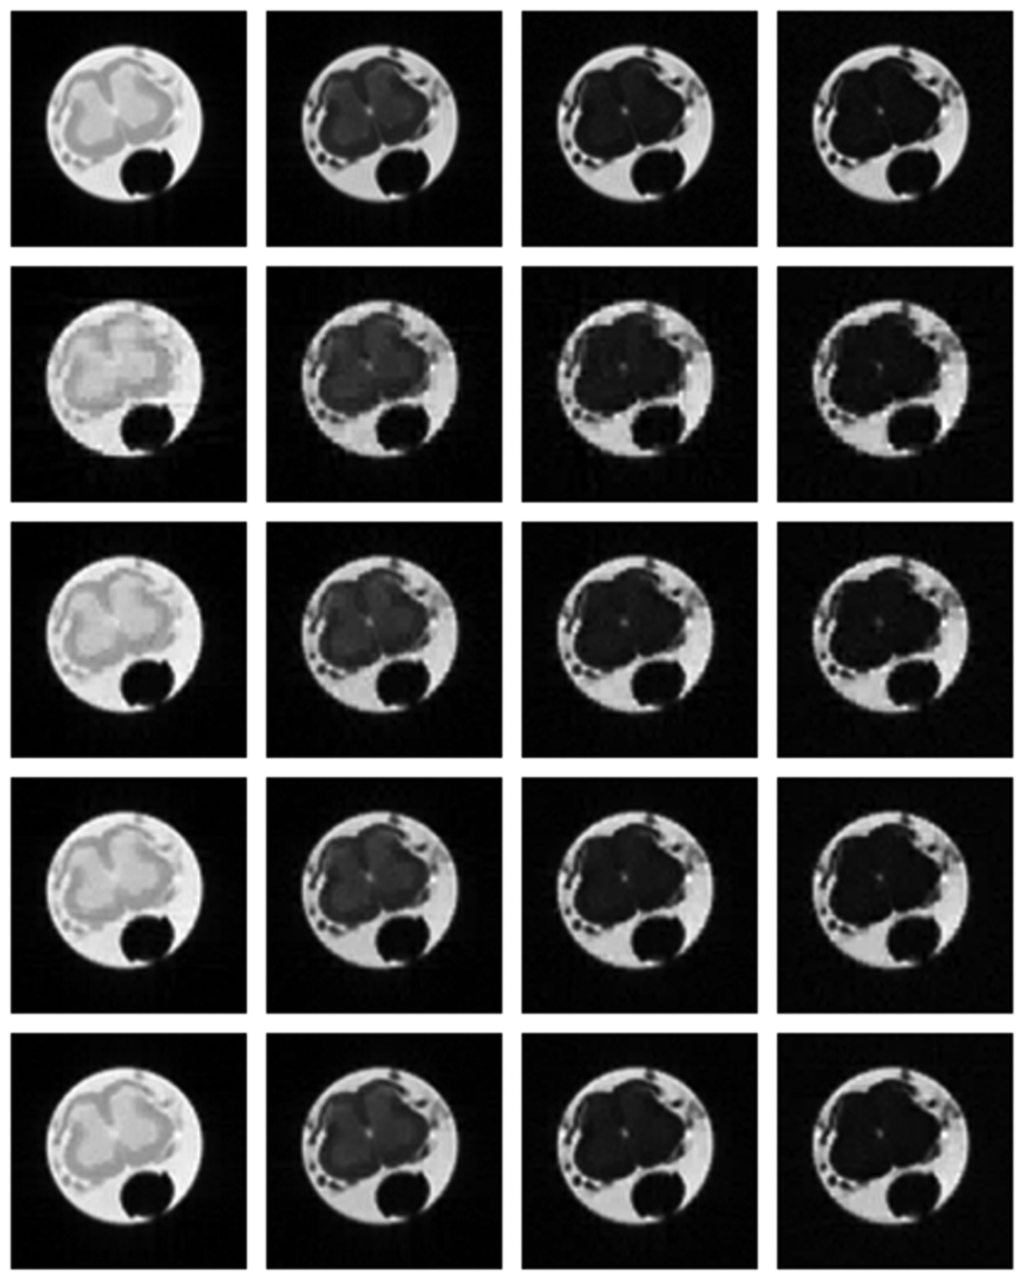

This work assumes that if the multi-echo MR images reconstructed from partial K-space scans are similar to those from full K-space scans, the corresponding T2 maps will be similar as well. This assumption is validated experimentally. In the following figure, we show the T2 maps for the ex vivo and in vivo data. The CPMG data were processed with software procedures developed in-house using MATLAB R2009b. Regularized non-negative least square (NNLS) analysis [16] was used to calculate the continuous T2 distributions. For the in vivo data, only the portion corresponding to the spinal cord is fit.

From Figure 7, the maps reconstructed from partial K-space data look almost the same as the map reconstructed from full K-space sampling. The difference in quality is more clearly visible from the difference maps shown in Figure 8. The contrast of the difference images are enhanced 10 times for visual clarity. It can be seen that for the same masks (for all echoes) the difference image shows large reconstruction error (almost white image). The reconstruction result improves when different sampling masks are used. But in either case, our proposed method with mixed prior optimization yields better results than the corresponding former techniques [6,7]. The best results are obtained (almost no reconstruction error) when mixed prior optimization is used with different sampling masks for each echo. One can also notice that the in general the ex vivo difference images are darker (less reconstruction error) compared to the in vivo images. This owes to the fact that in vivo images are more difficult to reconstruct.